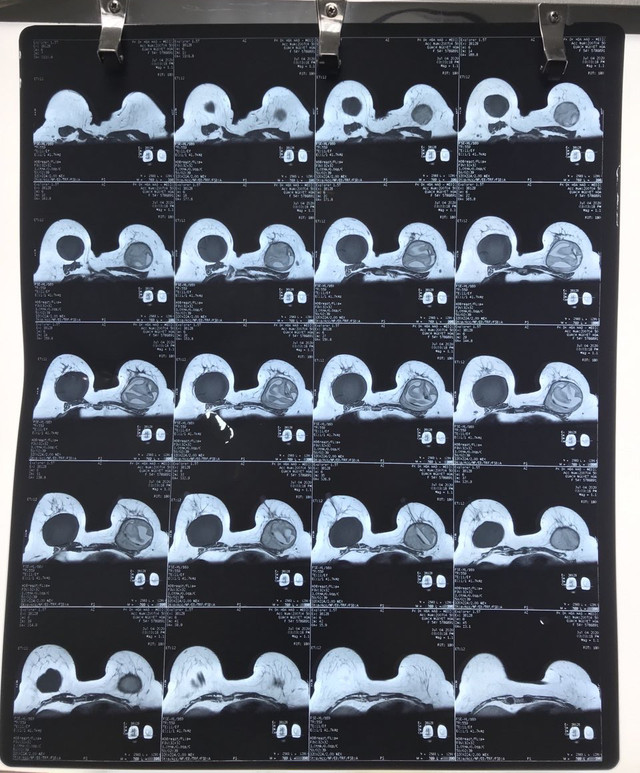

Hình chụp X-quang cho thấy túi ngực nhân tạo của chị H bị vỡ

Tại đây, bác sĩ cho biết chị H. bị vỡ túi ngực nhân tạo bên trái, nách trái có hạch lớn, bầu ngực bị biến dạng. Chị được bác sĩ tư vấn phẫu thuật lấy bỏ túi độn ngực hai bên, đồng thời làm xét nghiệm giải phẫu hạch và bao xơ xung quanh túi ngực để tầm soát ung thư vú. Với nguyện vọng có được "vòng 1" căng đẹp, chị H. xin ý kiến bác sĩ về việc đặt lại túi độn ngực.

BSCKII. Vũ Hữu Thịnh – Quản lý và điều hành, Phó trưởng Khoa Tạo hình – Thẩm mỹ BV ĐHYD TPHCM cho biết: "Túi ngực bên trái của người bệnh bị vỡ hoàn toàn và không phải là vật liệu được Bộ Y tế cấp phép trong phẫu thuật nâng ngực. Chúng tôi thực hiện phẫu thuật lấy bỏ túi ngực ở cả hai bên. Sau khi làm sạch, lấy hạch và bao xơ quanh túi ngực làm sinh thiết lạnh (giải phẫu bệnh tức thời), kết quả cho thấy sức khỏe của chị H. bình thường, chúng tôi đặt túi ngực mới theo nguyện vọng của chị".